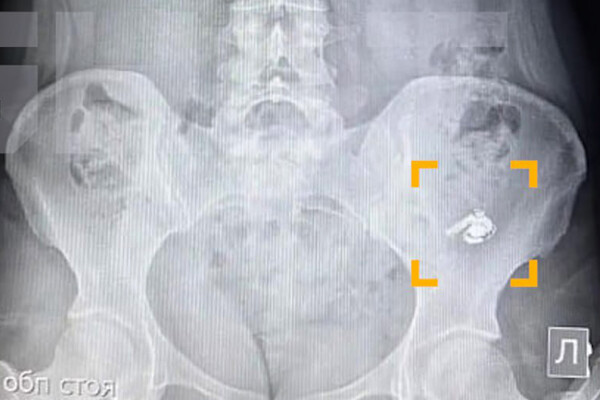

По словам уфимки по имени Мария, в момент глотания она почувствовала дискомфорт, но решила, что ей попалась крупная таблетка. Позже, обнаружив пропажу одного из наушников, девушка обратилась за медицинской помощью. В больнице ей сделали рентген, который подтвердил наличие инородного предмета в желудке.

Врачи решили не извлекать наушник, чтобы не спровоцировать осложнения, и рекомендовали дождаться его естественного выхода. Пациентку отпустили домой под наблюдение. Как рассказала Мария, устройство продолжало работать – при включении музыка воспроизводилась, однако услышать ее было невозможно.